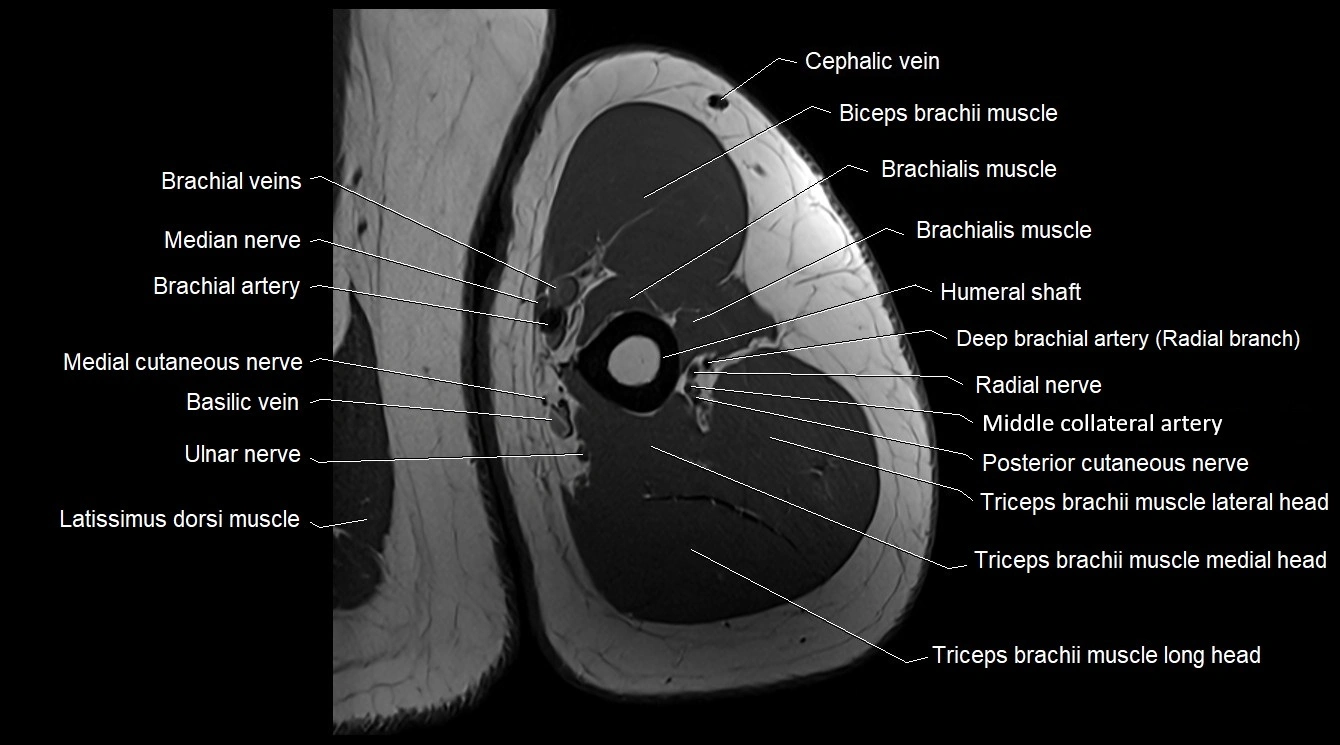

MRI image